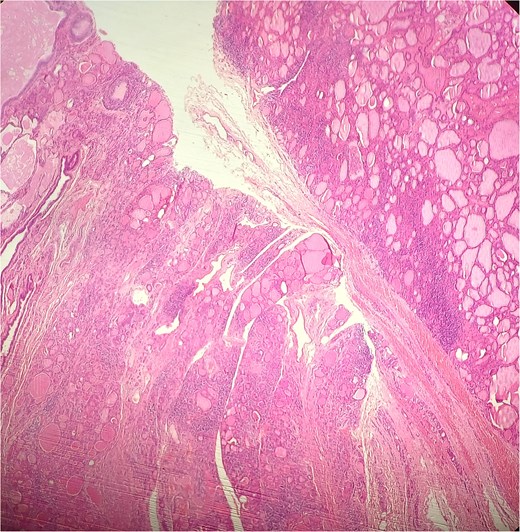

A 47-year-old woman with unremarkable medical history, presented with a 2 months history of neck mass along the midline. Physical examination revealed a 6 cm mobile, thyroid nodule without compressive symptoms. There was no associated erythema, fluctuance, tenderness or adhesion to adjacent structures. There was also no associated cervical lymphadenopathy. The rest of the physical exam was unremarkable. Laboratory tests including TSH, FT3, and FT4 revealed normal levels. On cervical ultrasound, there were a 62 mm left toto-lobar nodule classified as EU-TIRADS3, and an 11 mm right nodule, also classified as EU-TIRADS3. Fine-needle aspiration cytology concluded to a benign lesion classified as BETHESDA II. The patient reported respiratory discomfort in the supine position, leading to the indication for a lobectomy. Gross examination of the specimen revealed a toto-lobular nodule with a colloid appearance. It was well-circumscribed by a thin and regular fibrous capsule. The nodule measured 4 × 6 cm and exhibited areas of fibrous, whitish remodeling, as well as hemorrhagic and cystic changes. On microscopic examination, the nodule corresponded to a macro vesicular adenoma altered by fibrosis and hemorrhage. It was surrounded by a thin, regular, and intact fibrous capsule. However, at the periphery of the nodule, adjacent to the thyroid pseudo capsule, a 1.2 cm cystic ductal structure was observed. It showed pseudostratified ciliated columnar and squamous epithelial lining associated with thyroid follicles in the surrounding stroma (Figs 1 and 2). These thyroid follicles were bland with no papillary nuclear atypia or invasion (Fig. 3). The cyst was filled with a thin eosinophilic material (Fig. 4) Lymphocytic thyroiditis of mild severity was identified in the rest of the thyroid tissue. Based on these findings, the diagnosis of macro vesicular thyroid adenoma with ITTGDC and lymphocytic thyroiditis was made. After the surgery, the patient developed temporary dysphonia.

HE × 20: The cyst was lining with pseudostratified ciliated columnar cells and circumscribed with thyroid follicle within the cystic wall.